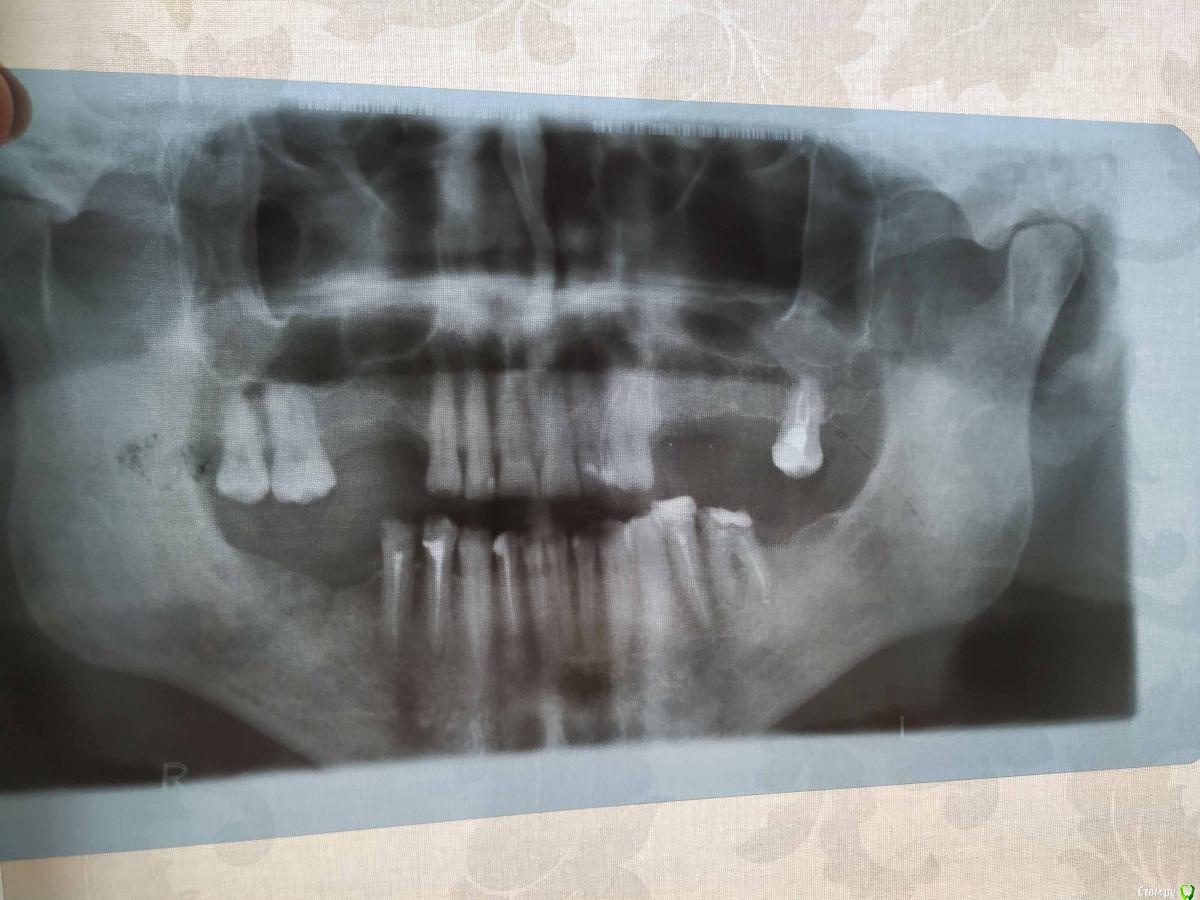

Владимир Серпухов Опубликовано 17 апреля, 2019 Поделиться Опубликовано 17 апреля, 2019 (изменено) Добрый день, хорошие моиЯ Владимир, 38 лет, проживаю в Серпухове, имплантация в Туле.Верхние зубы отсутствуют уже лет 15.Операцию начали 12.04.19 в 15.30, закончили в 16.00Затем цифровой панорам снимок - винты в кости, до гаймор пазух слава Богу не доставли.Сказали через 2 месяца приезжать.Ответьте на пару вопросов пожалуйста:1. Мне и правда не надо было синус-лифтов никаких делать?2. Слева врач предлагает имплант+имплавнт+последний зуб = один мост. На ваш взгляд верно? Я переживаю, что если свой зуб заболит, ето надо всю конструкцию имплантную снимать. Может все-таки свой зуб к имплантам не не надо? Изменено 17 апреля, 2019 пользователем Владимир Серпухов Ссылка на комментарий

Владимир Серпухов Опубликовано 17 апреля, 2019 Автор Поделиться Опубликовано 17 апреля, 2019 Добрый день, хорошие моиЯ Владимир, 38 лет, проживаю в Серпухове, имплантация в Туле.Верхние зубы отсутствуют уже лет 15.Операцию начали 12.04.19 в 15.30, закончили в 16.00Затем цифровой панорам снимок - винты в кости, до гаймор пазух слава Богу не доставли.Сказали через 2 месяца приезжать.Ответьте на пару вопросов пожалуйста:1. Мне и правда не надо было синус-лифтов никаких делать?2. Слева врач предлагает имплант+имплавнт+последний зуб = один мост. На ваш взгляд верно? Я переживаю, что если свой зуб заболит, ето надо всю конструкцию имплантную снимать. Может все-таки свой зуб к имплантам не не надо? Ссылка на комментарий